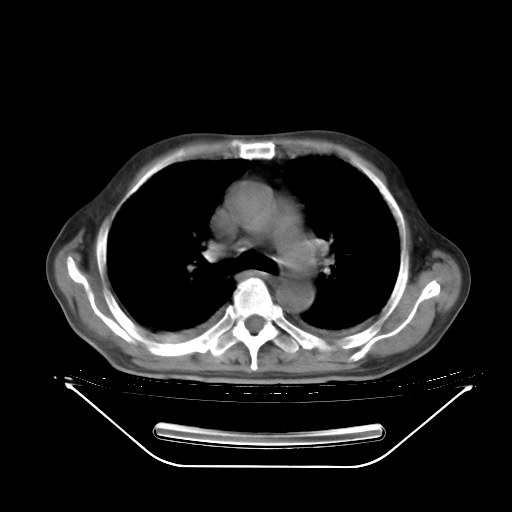

今天复查肺部CT,发现双肺广泛磨玻璃样改变。所以我把3月19日和5月9日相隔50天的肺部CT上传。请大家会诊。

2009年3月19日肺部CT片。

2009年3月19日肺部CT